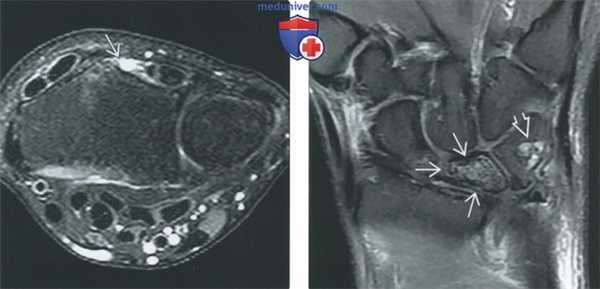

(Слева) МР-артрография, Т1, коронарный срез: определяется частичный разрыв ТФХ, поражающий медиальную часть его дистальной суставной поверхности. Большинство частичных разрывов ТФХ поражают проксимальную часть суставной поверхности и поэтому они визуализируется только после артрографии ДЛЛС.

(Справа) МР-артрография, выполненная после введения контраста в лучезапястный сустав, Т1ВИ, режим подавления сигнала от жира, коронарный срез: определяется косой линейный разрыв ТФХ на всю толщину. Этот разрыв распространяется от проксимальной лучевой поверхности до дистальной локтевой. (Слева) МР-артрография, Т1, коронарный срез: определяется сообщающийся дефект ТФХ с затеканием контраста от места его введения в лучезапястный сустав в ДЛЛС. Определяется линейный сигнал умеренной интенсивности от ДЛЛС отображающий смещенный фрагмент ТФХ. Также отмечается небольшой разрыв ПТС.

(Справа) МР-артрография, Т2 ВИ, режим подавления сигнала от жира, коронарный срез: у этого же пациента определяется фрагмент ТФХ с похожим сигналом, как и у ТФХ. (Слева) МР-артрография, Т1ВИ, сагиттальный срез: у этого же пациента определяется источник лоскутною фрагмента ТФХ. Изображения в сагиттальном срезе могут добавить значимость интерпретации МР-атрографии.

(Справа) МР-артрография, Т1 ВИ, аксиальный срез: у тою же пациента определяется смещенный фрагмент фиброзною хряща, заполняющий часть ДЛЛС. У пациента отмечалась боли при пронации и супинации кисти.